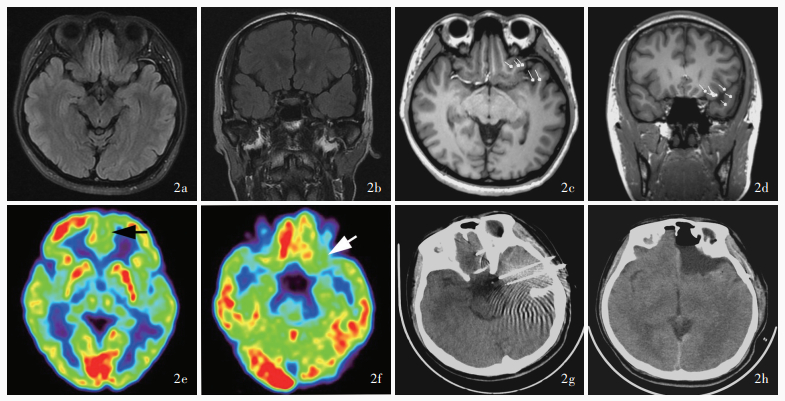

Sun K , Ren Z , Yang D , Wang X , Yu T , Ni D , Qiao L , Xu C , Gao R , Lin Y , Zhang X , Shang K , Chen X , Wang Y , Zhang G . Voxel-based morphometric MRI post-processing and PET/MRI co-registration reveal subtle abnormalities in cingulate epilepsy. Epilepsy Res, 2021, 171: 106568.

doi: 10.1016/j.eplepsyres.2021.106568